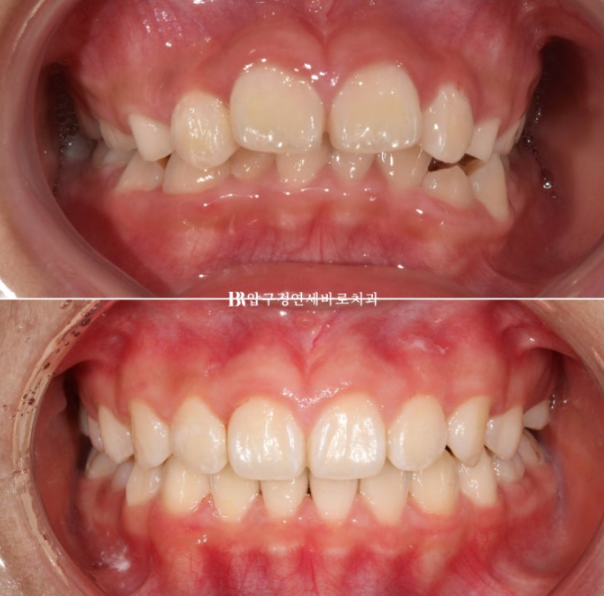

소아교정을 위해 찾아온 만 9세 어린이 입니다.

22.08

위 앞니가 아랫니를 가려서 안 보일 정도로 깊게 물리는 과개교합이고 윗니 돌출이 눈에 띕니다.

한달 반을 기다려서 첫 장치를 낀 것은 22년 9월부터이고 23년 6월까지 9개월간 첫 세트 장치를 모두 낀 후 모습입니다.

23.06

깊게 물리는 과개교합은 해소가 되었고 중심선도 잘 맞습니다.

앞니 돌출은 해소가 되었고 송곳니가 내려오는 중 입니다.